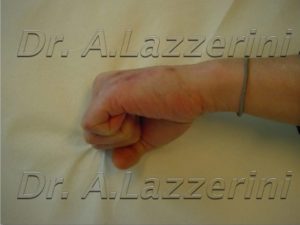

Allungamento.

Consolidazione del rigenerato.